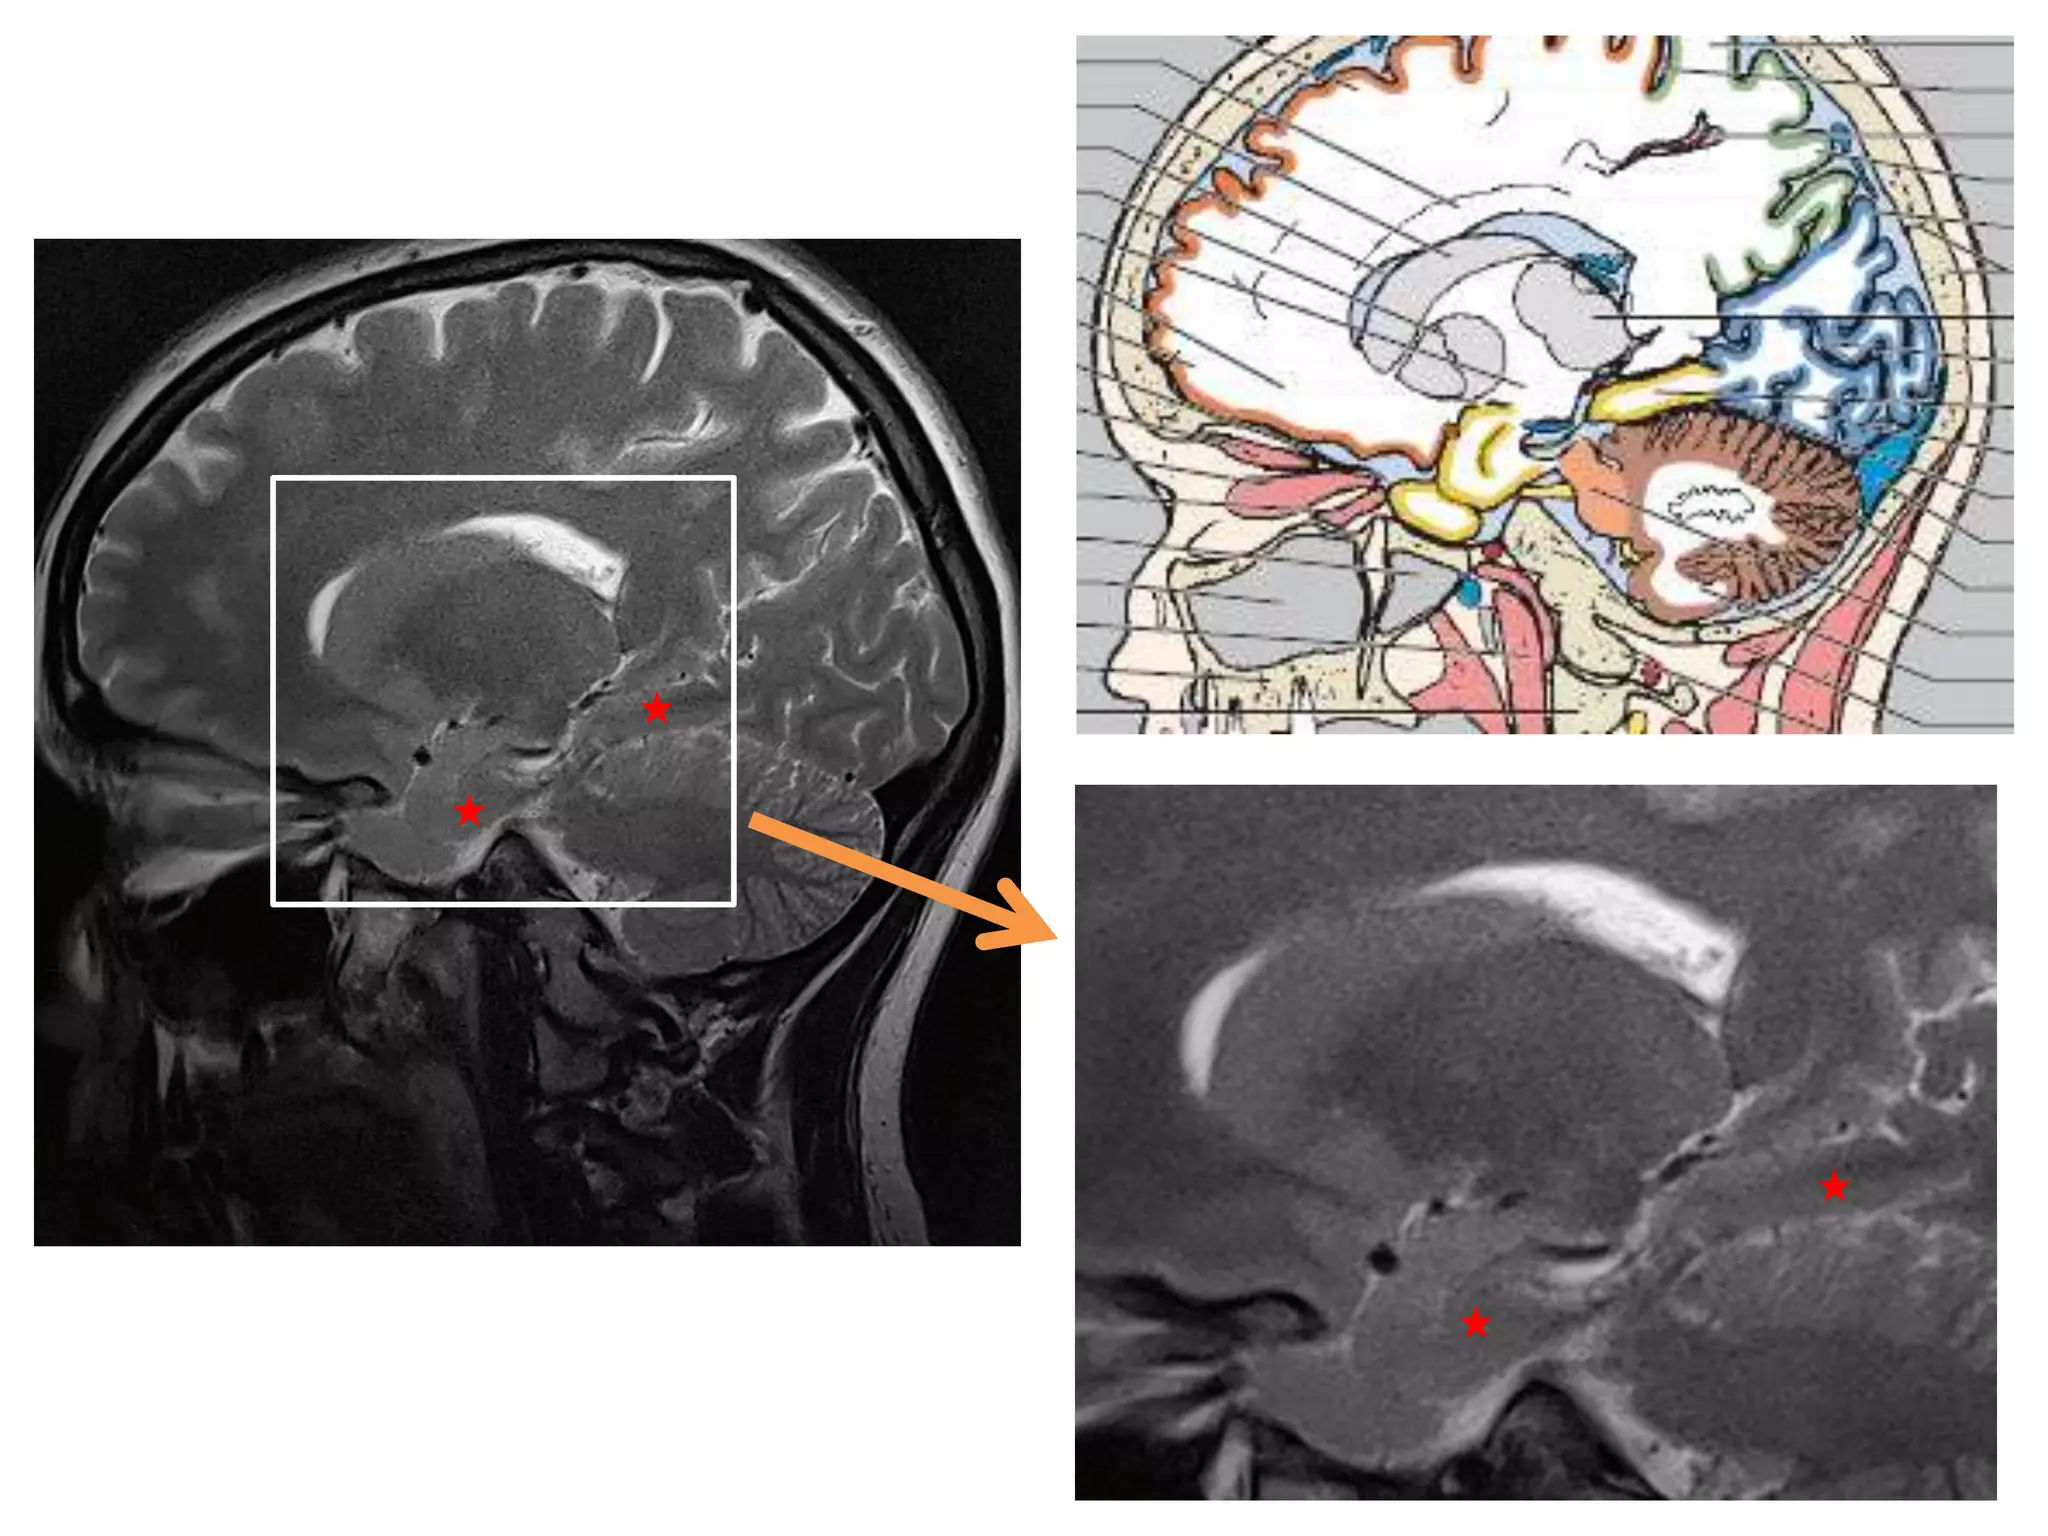

• Saggital and Coronal T1 weighted MRI – accurate

assessment of ventricles and C. callosum

• Mid Saggital section – for shape and configuration

of Aqueduct of Sylvius.

Saggital MRI : ‘C’ shaped , curving round the

thalamus.

• Radiology –

Axial MRI / CT : frontal horns separated by

S. pellucidum and posteriorly lateral ventricles diverge

and pass into temporal and occipital horns.

Coronal : frontal horns – inverted triangle

body – flattened

temporal horns – like ‘C’ on its sides.